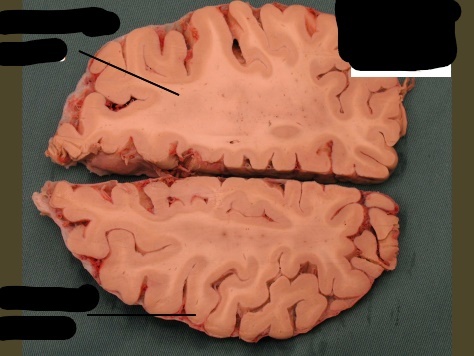

label, note important features

only portion of corona radiata seen right now are association fibers (which interconnect ipsilateral gyri) there are no internal capsule or lateral ventricles seen, indicating this cut is very rostral (pre-frontal cortex)